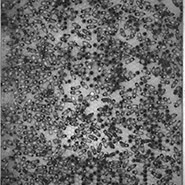

Many processes within the body are changed by the presence of cancer. These images show the response of microglia, immune defense cells in the brain, to cancer cells. When microglia encounter glioblastoma multiforme, one of the most aggressive brain cancers, they shift from a relaxed, elongated shape to a rounded, ready-for-combat conformation.

These images echo the work of Anna Atkins, a British botanist and photographer who used a contact printing technique called cyanotyping to capture the form of plants and algae. Emily Chen’s work similarly seeks to explore biological function, in this case the immune response to brain cancer, by capturing and comparing biological forms.